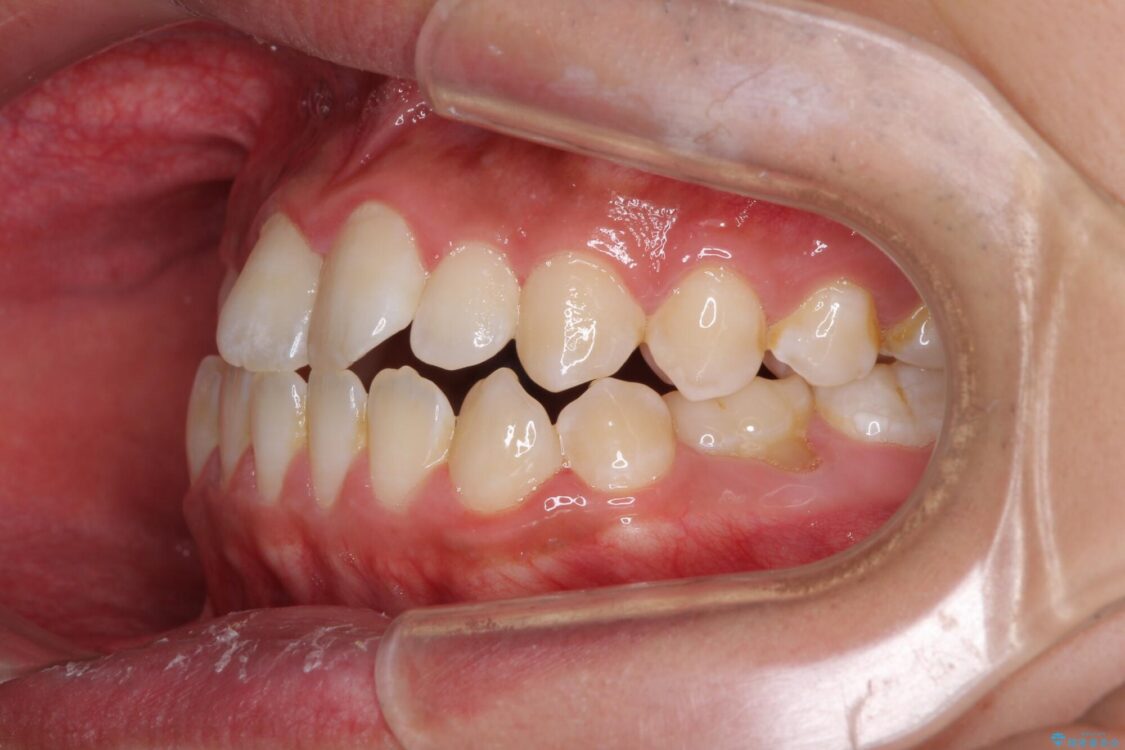

治療前

• 口元の突出感を改善 受け口傾向の咬み合わせの抜歯矯正 治療前画像

受け口傾向の咬み合わせと口元の突出感を気にして来院された患者様です。

受け口傾向特有の狭い上顎歯列であったため、歯列の拡大を補助装置で行い、下顎歯列全体を後方に移動させることとしました。

奥歯の咬み合わせを改善させた後、上下左右の小臼歯(下顎は残存乳歯)を計4本抜歯し、ワイヤー装置にて口元の突出感を改善しながら咬み合わせを整えることとしました。